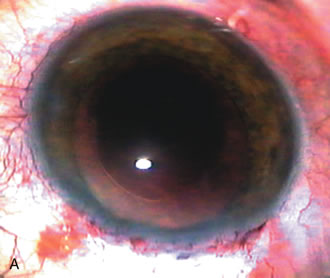

CASE 6: ANTICIPATED LENS EXTRACTION POST FAILED TRABECULECTOMY WITH ADVANCED DISC DAMAGE AND IOP OUTSIDE TARGET PRESSURE RANGE

The inflammation associated with lens extraction at any site usually causes complete failure of a marginal functioning bleb. In addition, pressure reduction by medical means is usually minimal in these recalcitrant cases, and combined surgery is indicated. In the past, these cases were approached with large-incision ECCE, clear corneal cataract incision, and bleb revision. Drawbacks included those mentioned earlier for large incision clear corneal cataract extraction, and bleb revision is often associated with conjunctival buttonholes, wound leaks, subconjunctival hematoma, destruction of friable sclera, and associated hypotony. With the advent of modern-day cataract surgery, a phacotrabeculectomy is often possible adjacent to the failed filter (Fig. 7). The ability to combine cataract extraction with implant and filtration surgery all through the same small incision has greatly improved outcomes for patients with marginal preoperative filters. There are several other viable options in this case. If the surgeon elects to remove the cataract through a temporal clear corneal incision, the bleb may be revised or a new adjacent filter fashioned. As mentioned earlier, revising a failed filter is technically challenging. If the surgeon believes it is not feasible to revise the filter or fashion a new one, a glaucoma drainage implant is a reasonable option combined with temporal lens extraction.172

Fig. 7. Phacotrabeculectomy adjacent to a failed filter in cataractous eye. The ability to combine small-incision cataract extraction with trabeculectomy all through the same incision adjacent to the failed filter allows the surgeon to work in a familiar superior area. Avoiding incisions into the existing bleb decreases conjunctival buttonholes, hypotony, operating room time, and subconjunctival bleeding. A. Appearance of failed bleb with exposure of superior temporal quadrant gained with a corneal traction suture. B. Prepare a limbus-based conjunctival flap and a scleral flap. C. This bleb is at high risk to fail again justifying the need for MMC, 0.2 mg/cc applied on a pledget for 4 minutes. D. Insert the keratome and perform phacotrabeculectomy in the usual fashion.